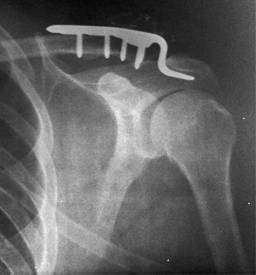

3) Placa gancho acromioclavicular. Fue descrita por primera vez en 1976 por Balser,17 se trata de una placa tipo LCP (por sus siglas en inglés Locking Compression Plate) de 3.5 mm, la cual se coloca en la cortical superior del tercio distal de la clavícula y como su nombre lo indica cuenta con un gancho que se introduce por debajo del acromion (Figura 3).